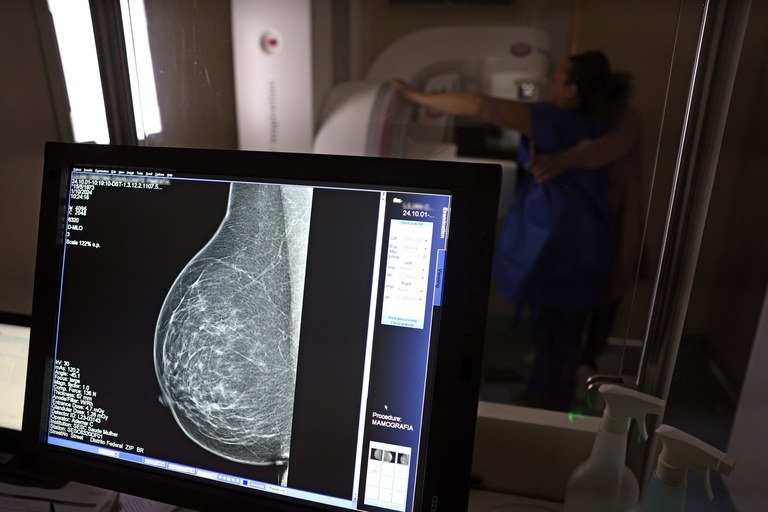

Câncer de mama ainda é o que mais mata mulheres no Brasil apesar dos avanços no rastreamento

O Brasil tem avançado no acesso à mamografia, mas ainda enfrenta desafios para transformar números em vidas salvas. Dados do Vigitel mostram que, entre 2007 e 2024, cresceu de 82,8% para 91,9% a proporção de mulheres de 50 a 69 anos que já fizeram o exame ao menos uma vez. O salto foi ainda maior entre as mais velhas e entre aquelas com menor escolaridade, sinal de que a política pública começa a alcançar grupos historicamente mais vulneráveis.

A expansão do exame para mulheres de 40 a 49 anos, anunciada em 2025, é outro marco. Até então, muitas só conseguiam acesso se apresentassem sintomas ou histórico familiar. Hoje, esse público já responde por 30% das mamografias feitas pelo SUS. O Ministério da Saúde também decidiu ampliar a faixa de rastreamento ativo até os 74 anos, reconhecendo que quase 60% dos casos de câncer de mama se concentram entre os 50 e 74 anos.

Apesar dos avanços, o cenário ainda preocupa. Estimativas do Inca apontam para 78.610 novos casos anuais de câncer de mama entre 2026 e 2028. O mastologista Bruno Giordano lembra que milhares de mulheres chegam aos serviços de saúde em estágios avançados da doença, quando as chances de cura diminuem. Para ele, o gargalo está no acesso desigual à mamografia, na demora para confirmar diagnósticos e no tempo até o início do tratamento.

O câncer de mama continua sendo o tipo mais comum e o que mais mata mulheres no país, com cerca de 37 mil mortes por ano. A mamografia, capaz de identificar tumores antes mesmo dos sintomas, pode elevar as chances de cura para até 95% quando realizada precocemente. Mas o exame precisa caminhar junto com políticas de informação, cumprimento da lei dos 60 dias para início da terapia e incentivo a hábitos saudáveis, como atividade física, alimentação equilibrada e redução do consumo de álcool.